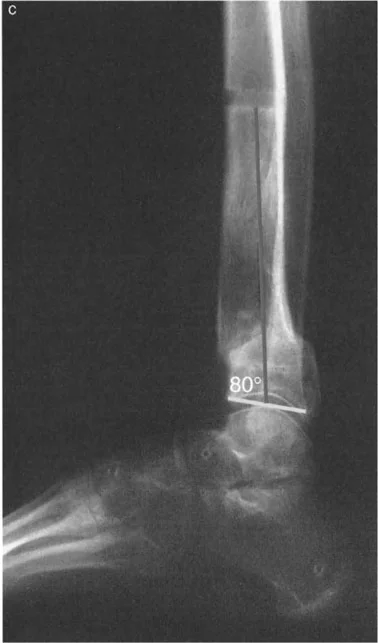

زاوية الكاحل الظهرية الظنبوبية (ADTA)

تُستخدم زاوية الكاحل الظهرية الظنبوبية (ADTA) كمعيار تشخيصي مهم لتقييم مدى تقوس الكاحل. وهي تقيس الزاوية بين محور عظم الظنبوب ومستوى عظم الكاحل. في الوضع الطبيعي، تسمح هذه الزاوية بحركة كافية لثني القدم للأعلى. أي انحراف عن هذه الزاوية الطبيعية يمكن أن يشير إلى وجود تقوس أو تشوه.

- صورة توضح تقلصًا في الكاحل بزاوية 20 درجة.

- قياس نطاق الحركة (Range of Motion): تقييم قدرة الكاحل والقدم على الثني للأعلى والأسفل، والقلب للداخل والخارج. يتم قياس زاوية الكاحل الظهرية الظنبوبية (ADTA) لتحديد درجة تقوس الكاحل.

- تعتبر الأشعة السينية ضرورية لتقييم العظام، وتحديد وجود أي كسور، سوء التئام، نتوءات عظمية، أو تشوهات هيكلية مثل تقوس الظنبوب البعيد أو عظم الكاحل المسطح.

- تساعد في قياس الزوايا المختلفة، مثل ADTA، لتحديد درجة تقوس الكاحل.

- صورة شعاعية توضح تقلصًا في الكاحل بزاوية 20 درجة.